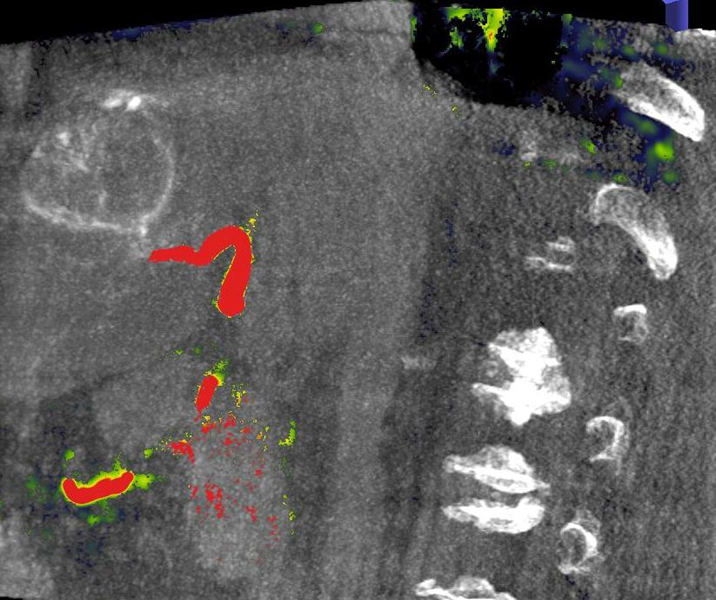

Die Selektive Interne Radiotherapie (SIRT) wird in der Fachliteratur auch Radioembolisation (RE) genannt. Hierbei werden gezielt kleine, radioaktive Kügelchen, sog. Mikrosphären, über den Katheter (siehe TACE) von mehreren Positionen in der Leber mit dem Blutstrom in das gut durchblutete Tumorgewebe gebracht und bleiben dort in den kleinen Gefäßen "stecken", die den Tumor ernähren. Von dort bestrahlt das in den Kügelchen enthaltene radioaktive Element Yttrium-90 über mehrere Tage hinweg das Tumorgewebe und zerstört es selektiv. Dieses Verfahren kann bei Leberkrebs oder -metastasen eingesetzt werden, wenn die Herde trotz Chemotherapie weiter wachsen und nicht chirurgisch oder mittels RFA und TACE behandelbar sind.

Abbildung Körper: Schematische Darstellung des Zugangsweges bei SIRT-Therapie über die Leistenarterie. Die arteriellen tumorversorgenden Gefäße in der Leber werden selektiv dargestellt und von dort wird die Therapie lokal appliziert. (Bildrechte beim Thieme-Verlag!)